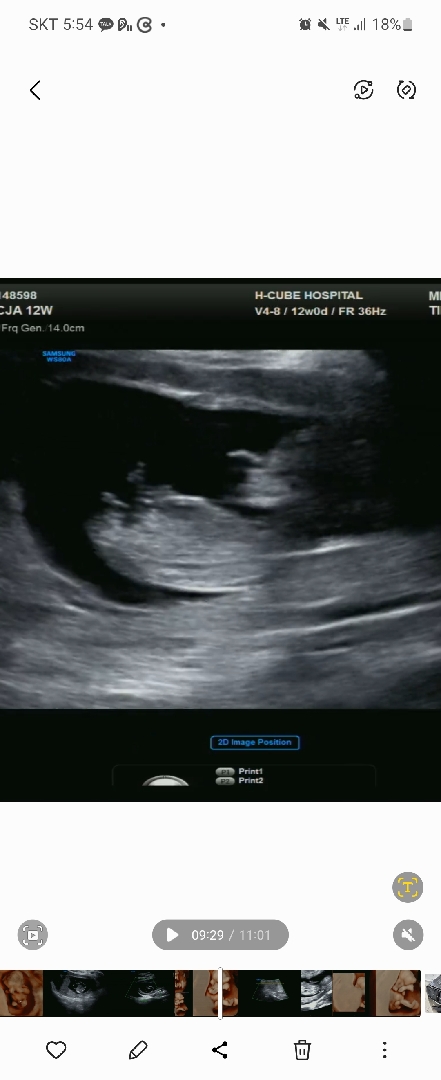

1차기형아검사 후 성별넘궁금해요

사진하나밖에 안올라가나봐요 ㅜㅜ 하나도 모르겟어요 각도법은 더더욱 ㅋㅋ다리밑을봐도 첫째둘째.낳은게.너무 오래되서 긴가민가해요 ㅠㅠ

우와 셋째 가지신거에요?! ㅎㅎ 다리랑 척추가 일자로되있으면 딸일확률이 높대요

네넷 어쩌다보니 셋째가 ㅎㅎㅎ 다리랑척추가 일자라..ㅜㅜ 너무어렵네요